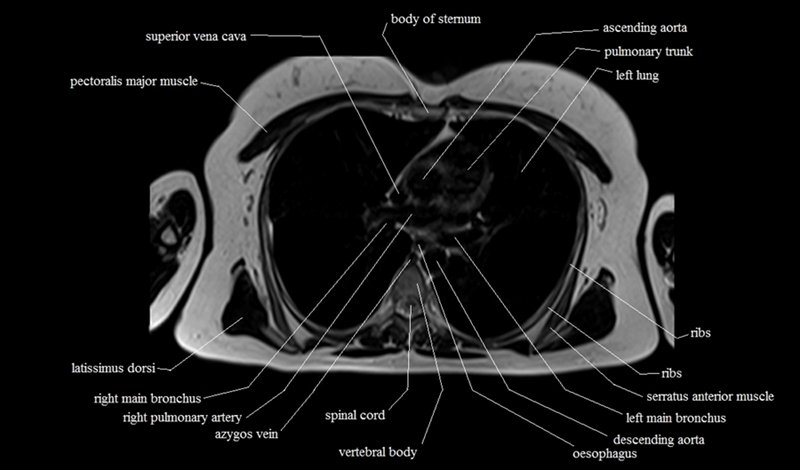

MRI Axial Cross Sectional Anatomy of Chest

This MRI chest (thorax) axial cross sectional anatomy tool is absolutely free to use. Use the mouse scroll wheel to move the images up and down, or alternatively, use the tiny arrows (→) on both sides of the image to navigate through the images. For a more detailed view, double-click the image to view it in full screen, and use the menu in the top right-hand corner to view individual slides or play them in a loop.